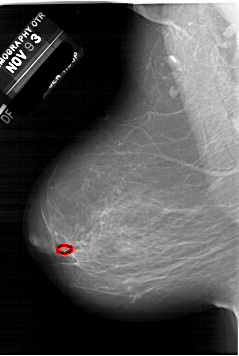

A_1952_1.LEFT_CC

LEFT_CC LINES 6151 PIXELS_PER_LINE 4051 BITS_PER_PIXEL 12 RESOLUTION 43.5 OVERLAY

FILE: A_1952_1.LEFT_CC.OVERLAY

TOTAL_ABNORMALITIES 1

ABNORMALITY 1

LESION_TYPE CALCIFICATION TYPE PLEOMORPHIC DISTRIBUTION CLUSTERED

ASSESSMENT 4

SUBTLETY 2

PATHOLOGY BENIGN

TOTAL_OUTLINES 1

BOUNDARY